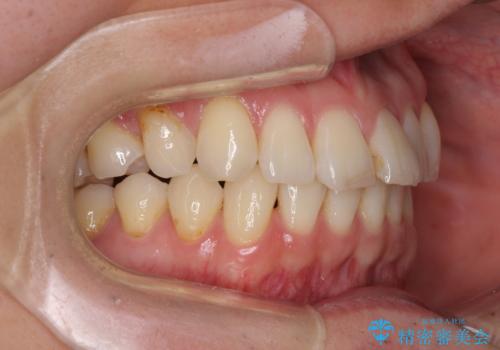

- 以前矯正治療を行ったものの、思い通りの仕上がりではなく、更には後戻りが気になってきたとのことで来院された患者様です。

上顎右側の第一小臼歯が動きにくい歯であり、以前矯正治療を行った際に傾斜した位置のまま終了したことと、それに伴い後戻りで歯列が波打っているようになっていることを大変気にしていらっしゃいました。